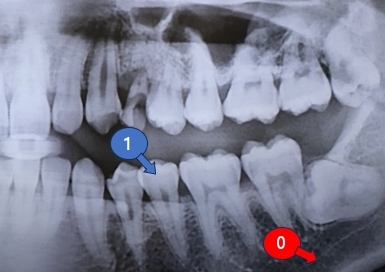

Detector에는 반도체가 들어가는데요. 두 가지 타입이있어요. 1. TFT / 2. CMOS 이죠. TFT는 주로 FPD(Flat Panel Display)에 들어가는 얅은(Thin) 박막(Film)의 트랜지스터(Transistor)에요. 트랜지스터는 전하의 이동 스위치 역할을 하죠. 예를 들면, 치아 X-ray 이미지를 떠올려보죠. 뼈가 있는 부분은 흰색으로 나오죠. 빛이 반사되니깐요. 여기는 디지털입장에서 보면 '1'로 처리해야합니다. 빛이 반사되서 돌아오니깐요. 반대로, 잇몸 같이 빛이 부딪치지 않은 곳들은 0으로 처리해야겠죠. 빛이 없으니깐요.